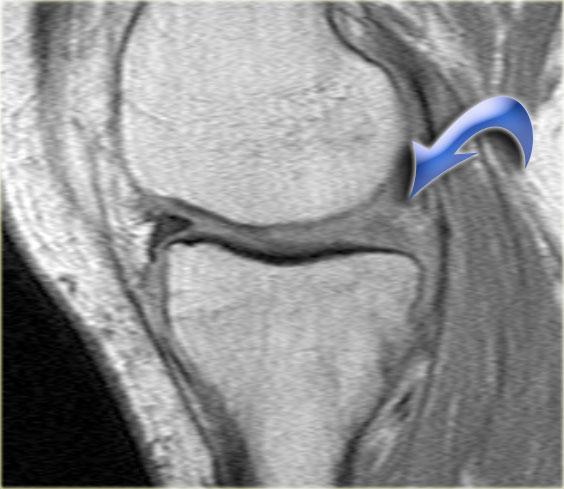

Đây là một trường hợp rách chân sụn chêm trong khác.

Lưu ý rằng sừng sau không còn bám vào xương chày.

Thay vào đó, có thể thấy một khoảng hở (mũi tên cong).

Những tổn thương rách này rất dễ bị bỏ sót khi người đọc nhầm tưởng sừng sau vẫn bình thường.